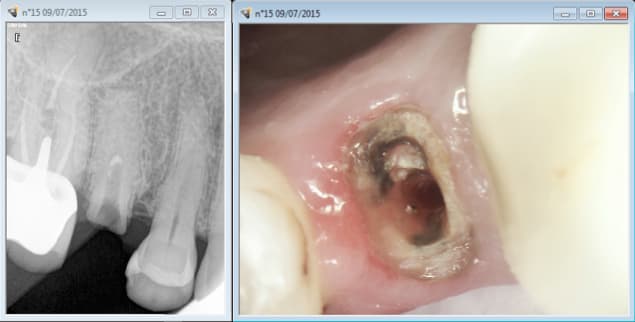

Oui oui la saison touristique bat son plein en Bretagne. On commence a avoir des urgences exotiques d'ile de France. L'important est de bien considérer son patient hein ?

Notez les endos réalisées conformément aux recommandations HAS.......